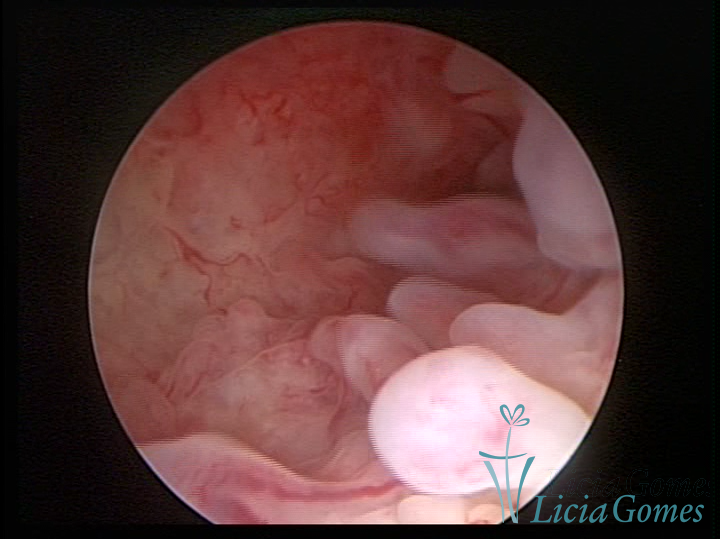

Este pode apresentar uma gama variável de aspectos macroscópicos, com aspecto pseudopolipoide; lembrando tecido cerebroide ou com reação deciduoide;a vascularização superficial é mais evidente e com vasos em formatos de saca-rolha ou espirais visualizando também a vascularização com atípias, com aumento do calibre dos vasos superficiais, pode ser encontrado também tecido em necrose, poderá haver um pequenos dendritos (papilomatoso).